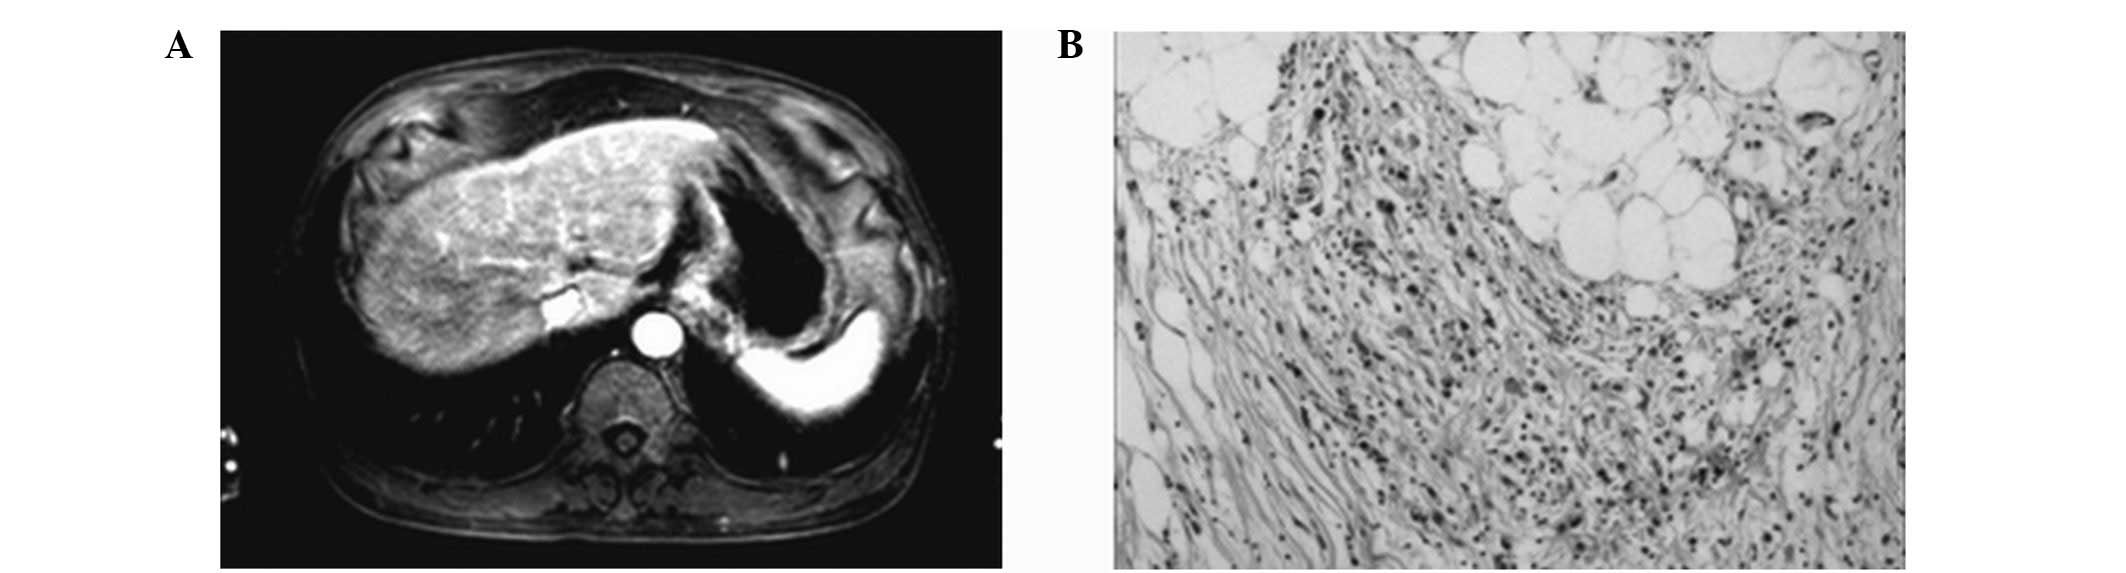

Thick tortuous folds or lobulated filling defects in the cardia or fundus. Right gastroepiploic artery inferiorly and left gastroepiploic artery and short gastric arteries superiorly fundus of the stomach. Results of surgical treatment of carcinoma of the esophagus and gastric cardia. The collection of cases presented here comprises only that material which is rare in our experience or quite new to us.

Cain jc jordan gl jr comfort mw gray hk. J am med assoc. The gas tric fundus is dened as the portion of the stomach craniad to the gastric car dia. Commonly accompanying this are abnormally dilated short gastric veins which pass from the splenic vein to encircle the gastric fundus and form gastric fundal varices.